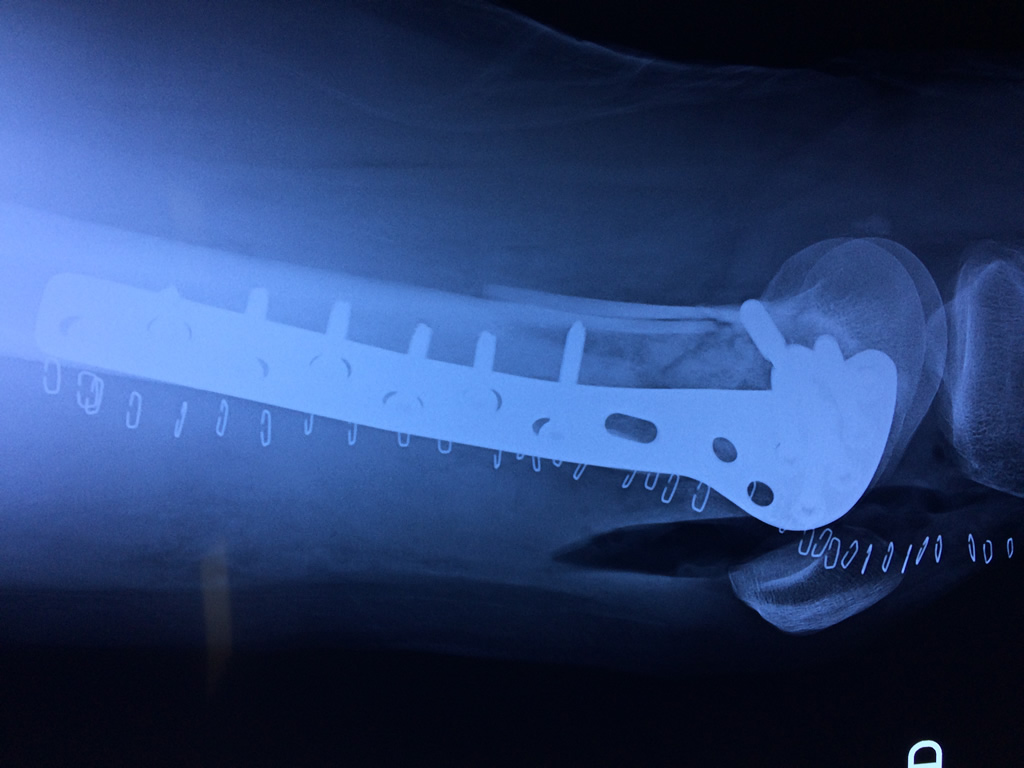

Húmero - Fémur